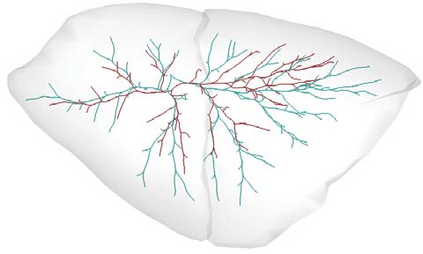

Recent advances in imaging techniques have enabled us to visualize lung tumors or nodules in early-stage cancer. However, the positions of nodules can change because of intraoperative lung deflation, and the modeling of pneumothorax-associated deformation remains a challenging issue for intraoperative tumor localization. In this study, we introduce spatial and geometric analysis methods for inflated/deflated lungs and discuss heterogeneity in pneumothorax-associated deformation. Contrast-enhanced CT images simulating intraoperative conditions were acquired from live Beagle dogs. Deformable mesh registration techniques were designed to map the surface and subsurface tissues of lung lobes. The developed framework addressed local mismatches of bronchial tree structures and achieved stable registration with a Hausdorff distance of less than 1 mm and a target registration error of less than 5 mm. Our results show that the strain of lung parenchyma was 35% higher than that of bronchi, and that subsurface deformation in the deflated lung is heterogeneous.